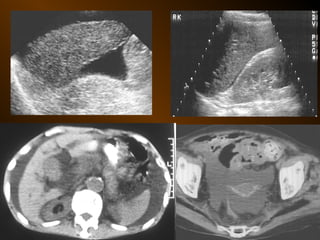

• SIÊU ÂM

– Phản âm trống, chuyển dịch

– Lượng ít

– Bản chất dịch

– Phản âm, chất chứa, vỏ bọc ?